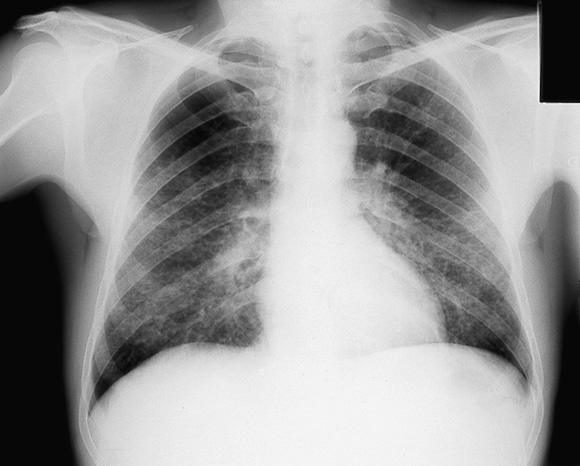

8: Pneumonitis caused by varicella–zoster virus

Chest x-ray showing interstitial pneumonitis in an otherwise healthy adult with chickenpox. Pneumonitis occurs in about 1 in 400 cases of adult infection and may be particularly severe in pregnancy.